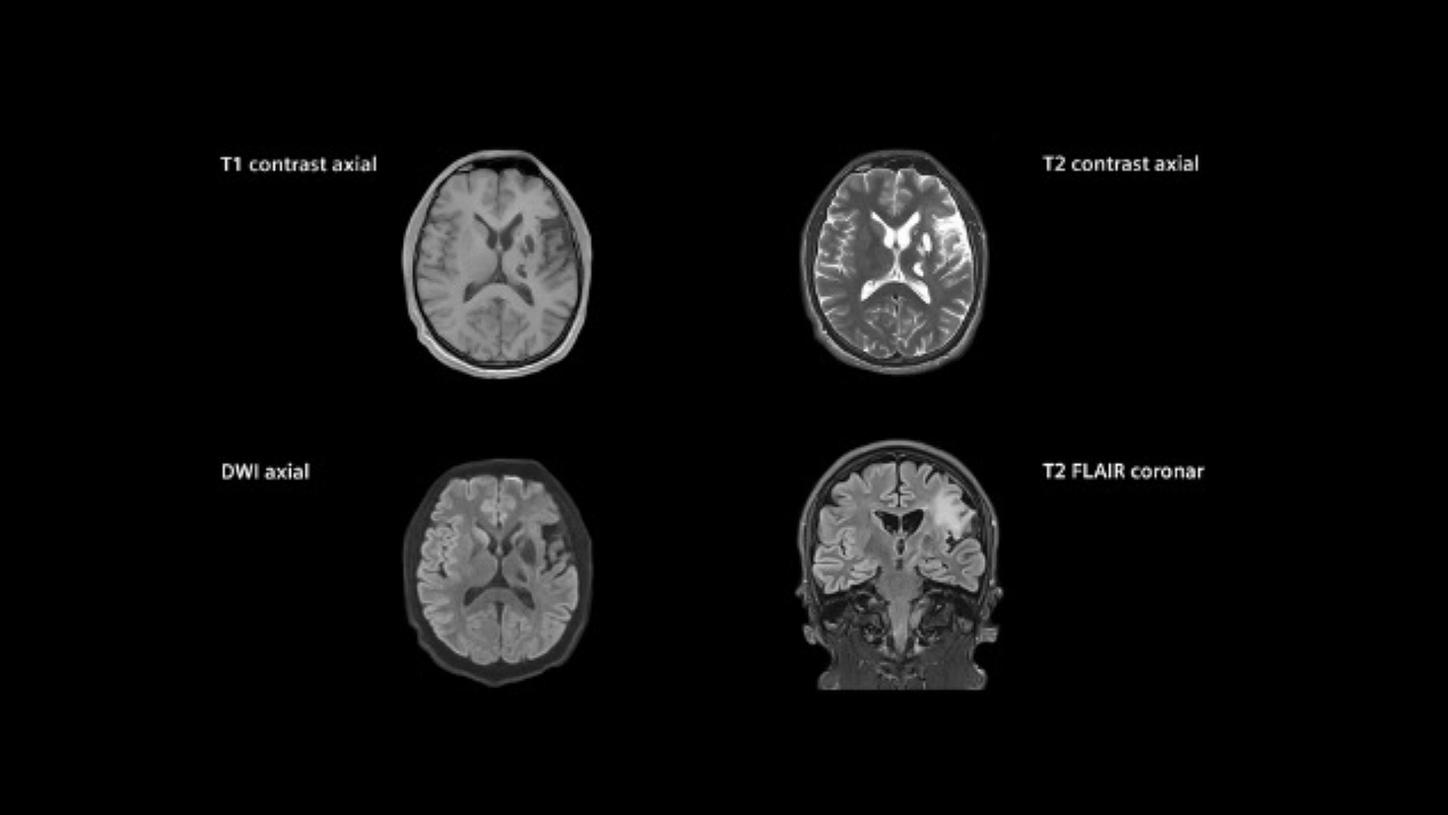

MAGNETOM Vida: Standard stroke protocol

GOBrain1) allows push-button brain exams in 5 minutes2)